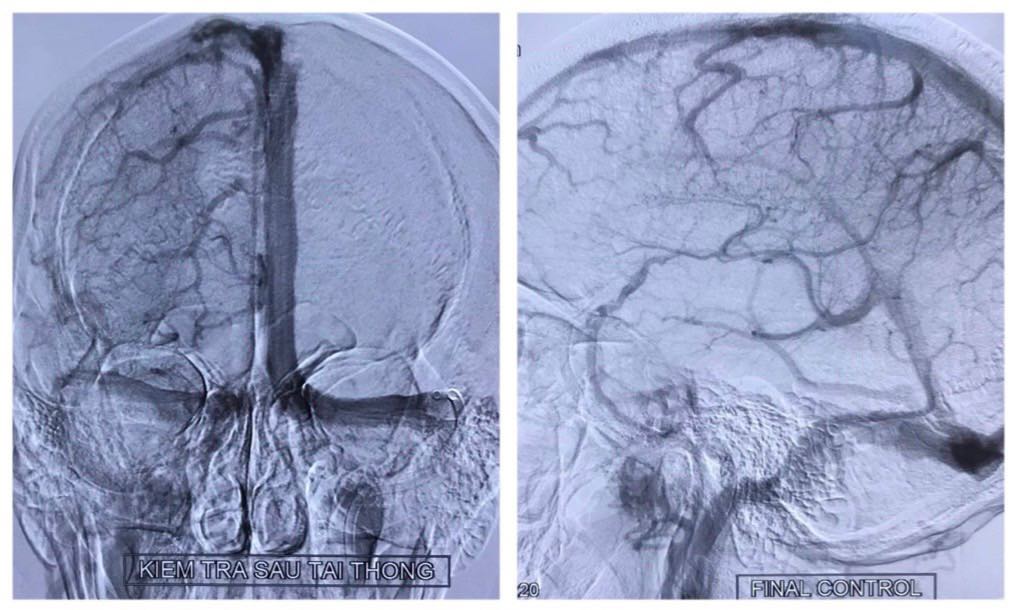

Phim chụp cộng hưởng từ sọ não nhanh chóng được thực hiện cho phép chẩn đoán tình trạng huyết khối gây tắc hoàn toàn hệ thống các xoang tĩnh mạch nội sọ (các xoang này có chức năng dẫn lưu phần lớn máu não trở về tim, trong trường hợp tắc có thể gây ứ trệ, sung huyết, xuất huyết, thiếu máu não). Bệnh nhân được điều trị chống đông và can thiệp lấy bỏ huyết khối cấp cứu.

Can thiệp nội mạch cho phép loại bỏ nhanh chóng huyết khối và tái lập lại tuần hoàn não, qua đó tránh được các biến chứng không mong muốn như thiếu máu hoặc chảy máu não.

Ở trường hợp ca bệnh này, sau khoảng gần hai giờ liên tục, rất nhiều huyết khối được lấy bỏ. Phim chụp sau can thiệp cho thấy các xoang tĩnh mạch tái thông hoàn toàn, không có tình trạng ứ trệ các tĩnh mạch não. Các cơn đau đầu, sau đó cũng nhanh chóng biến mất, chức năng vận động cảm giác hoàn toàn bình thường.

Trường hợp của bệnh nhân T, biểu hiện đau đầu nặng do huyết khối lan tỏa ở hầu hết các hệ thống xoang là những yếu tố đưa đến quyết định can thiệp hút huyết khối cơ học. Sau can thiệp gần như tất cả huyết khối đã được lấy bỏ, bệnh nhân tiến triển lâm sàng tốt và không có biến chứng nào xuất hiện cho phép chúng ta hy vọng về một kết quả khả quan.